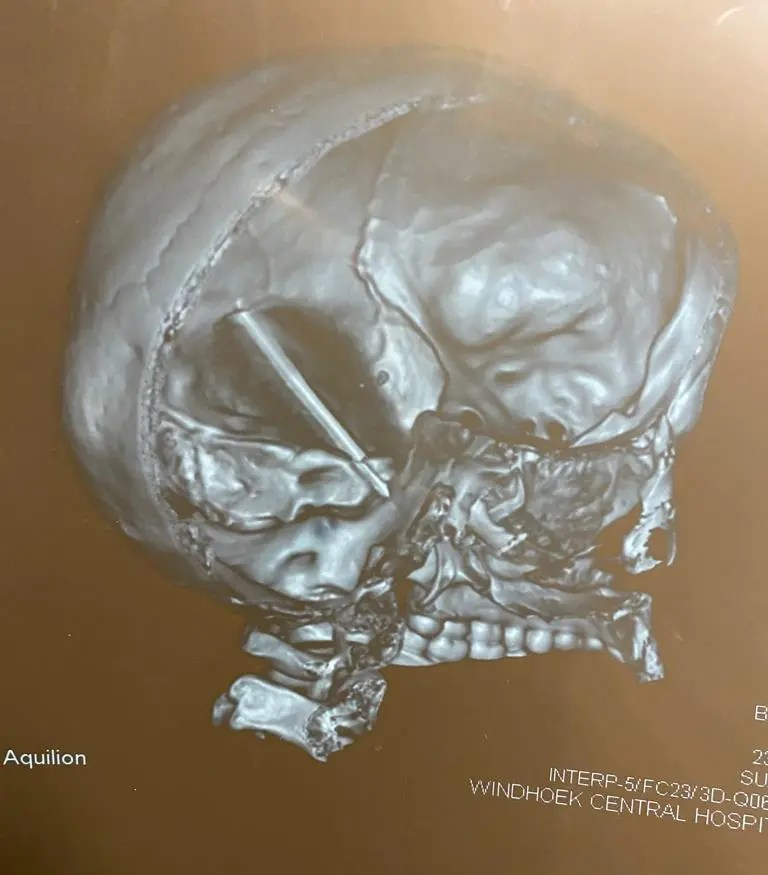

The work we do

S.T.D Neurosurgical Health Centre